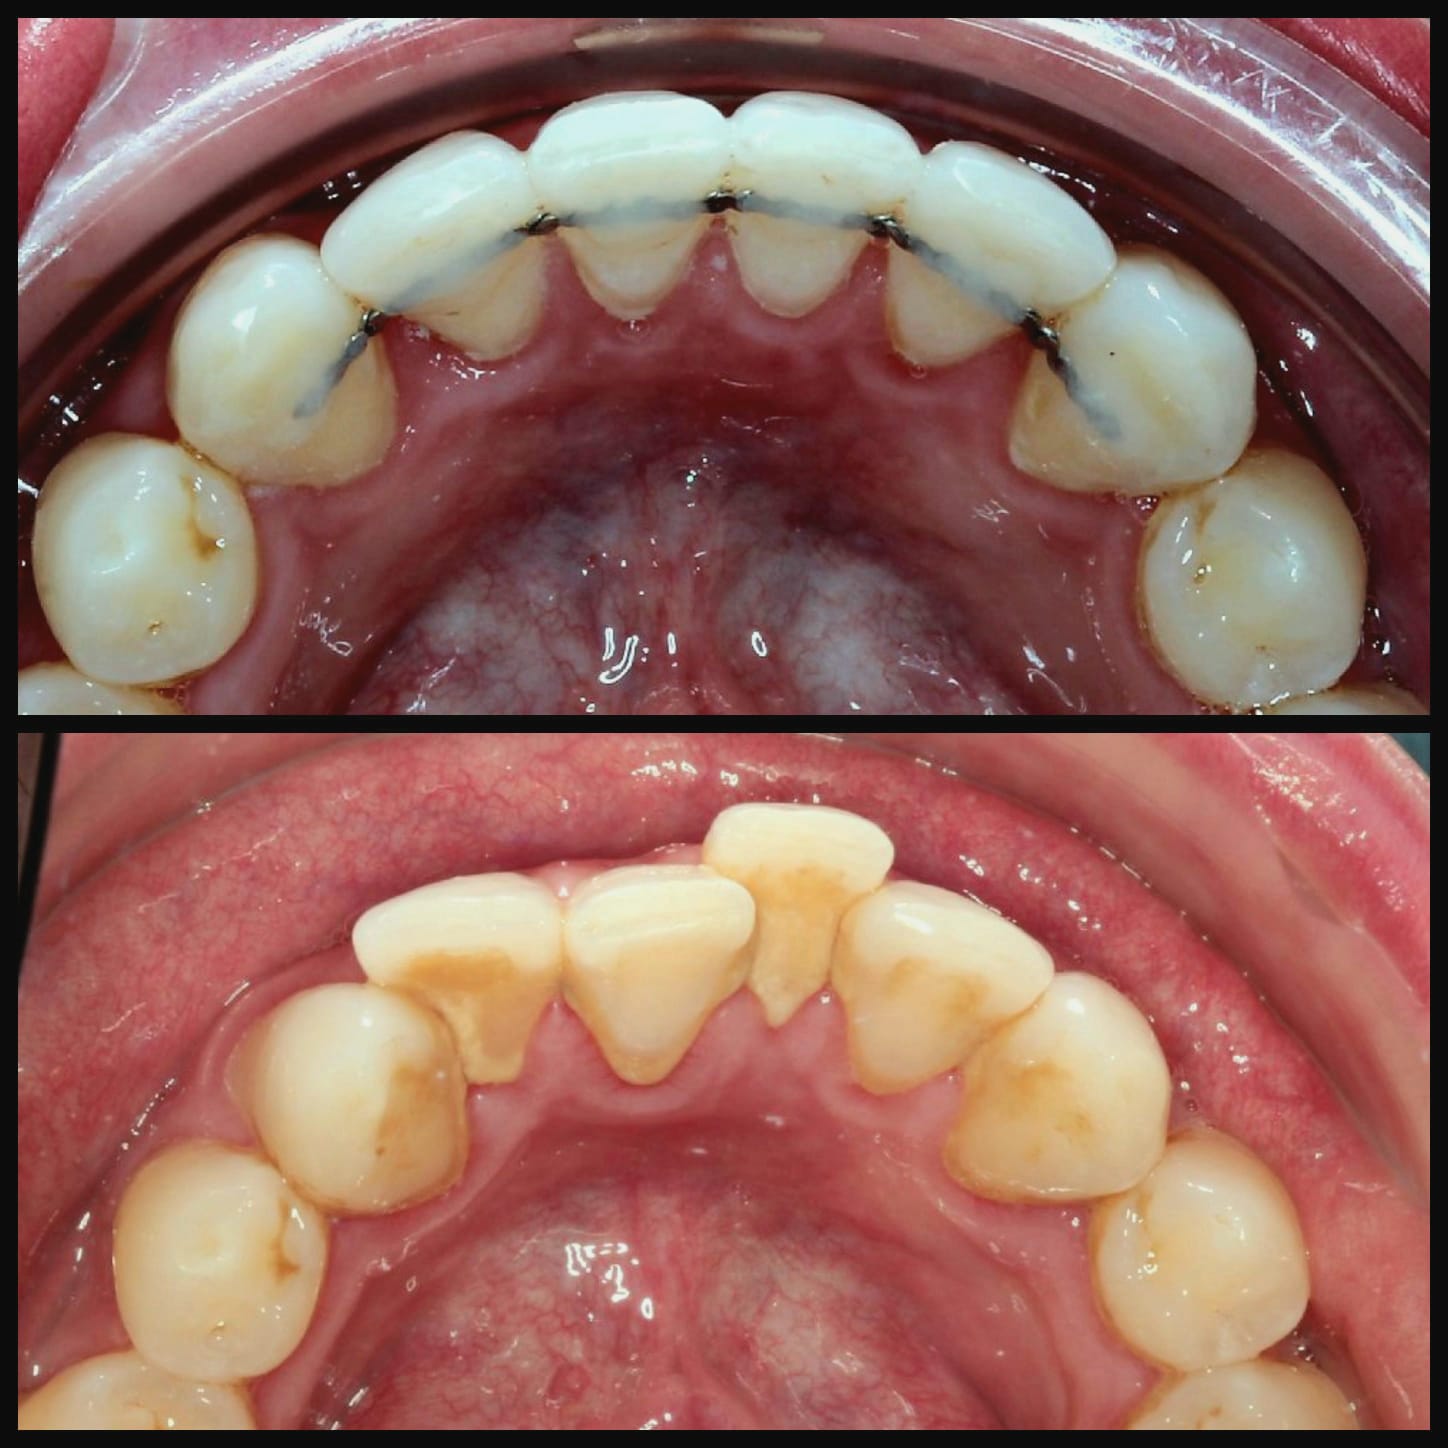

Invisalign is a well-known system for straightening teeth in the most discreet way. It works by using a series of clear aligners that fit comfortably over the teeth to gently move them into the desired position over time. There are no fixed brackets or wires used, in fact, the aligners are completely removable.

Virtually invisible way to straighten your teeth

Removable aligners make eating and dental care easy